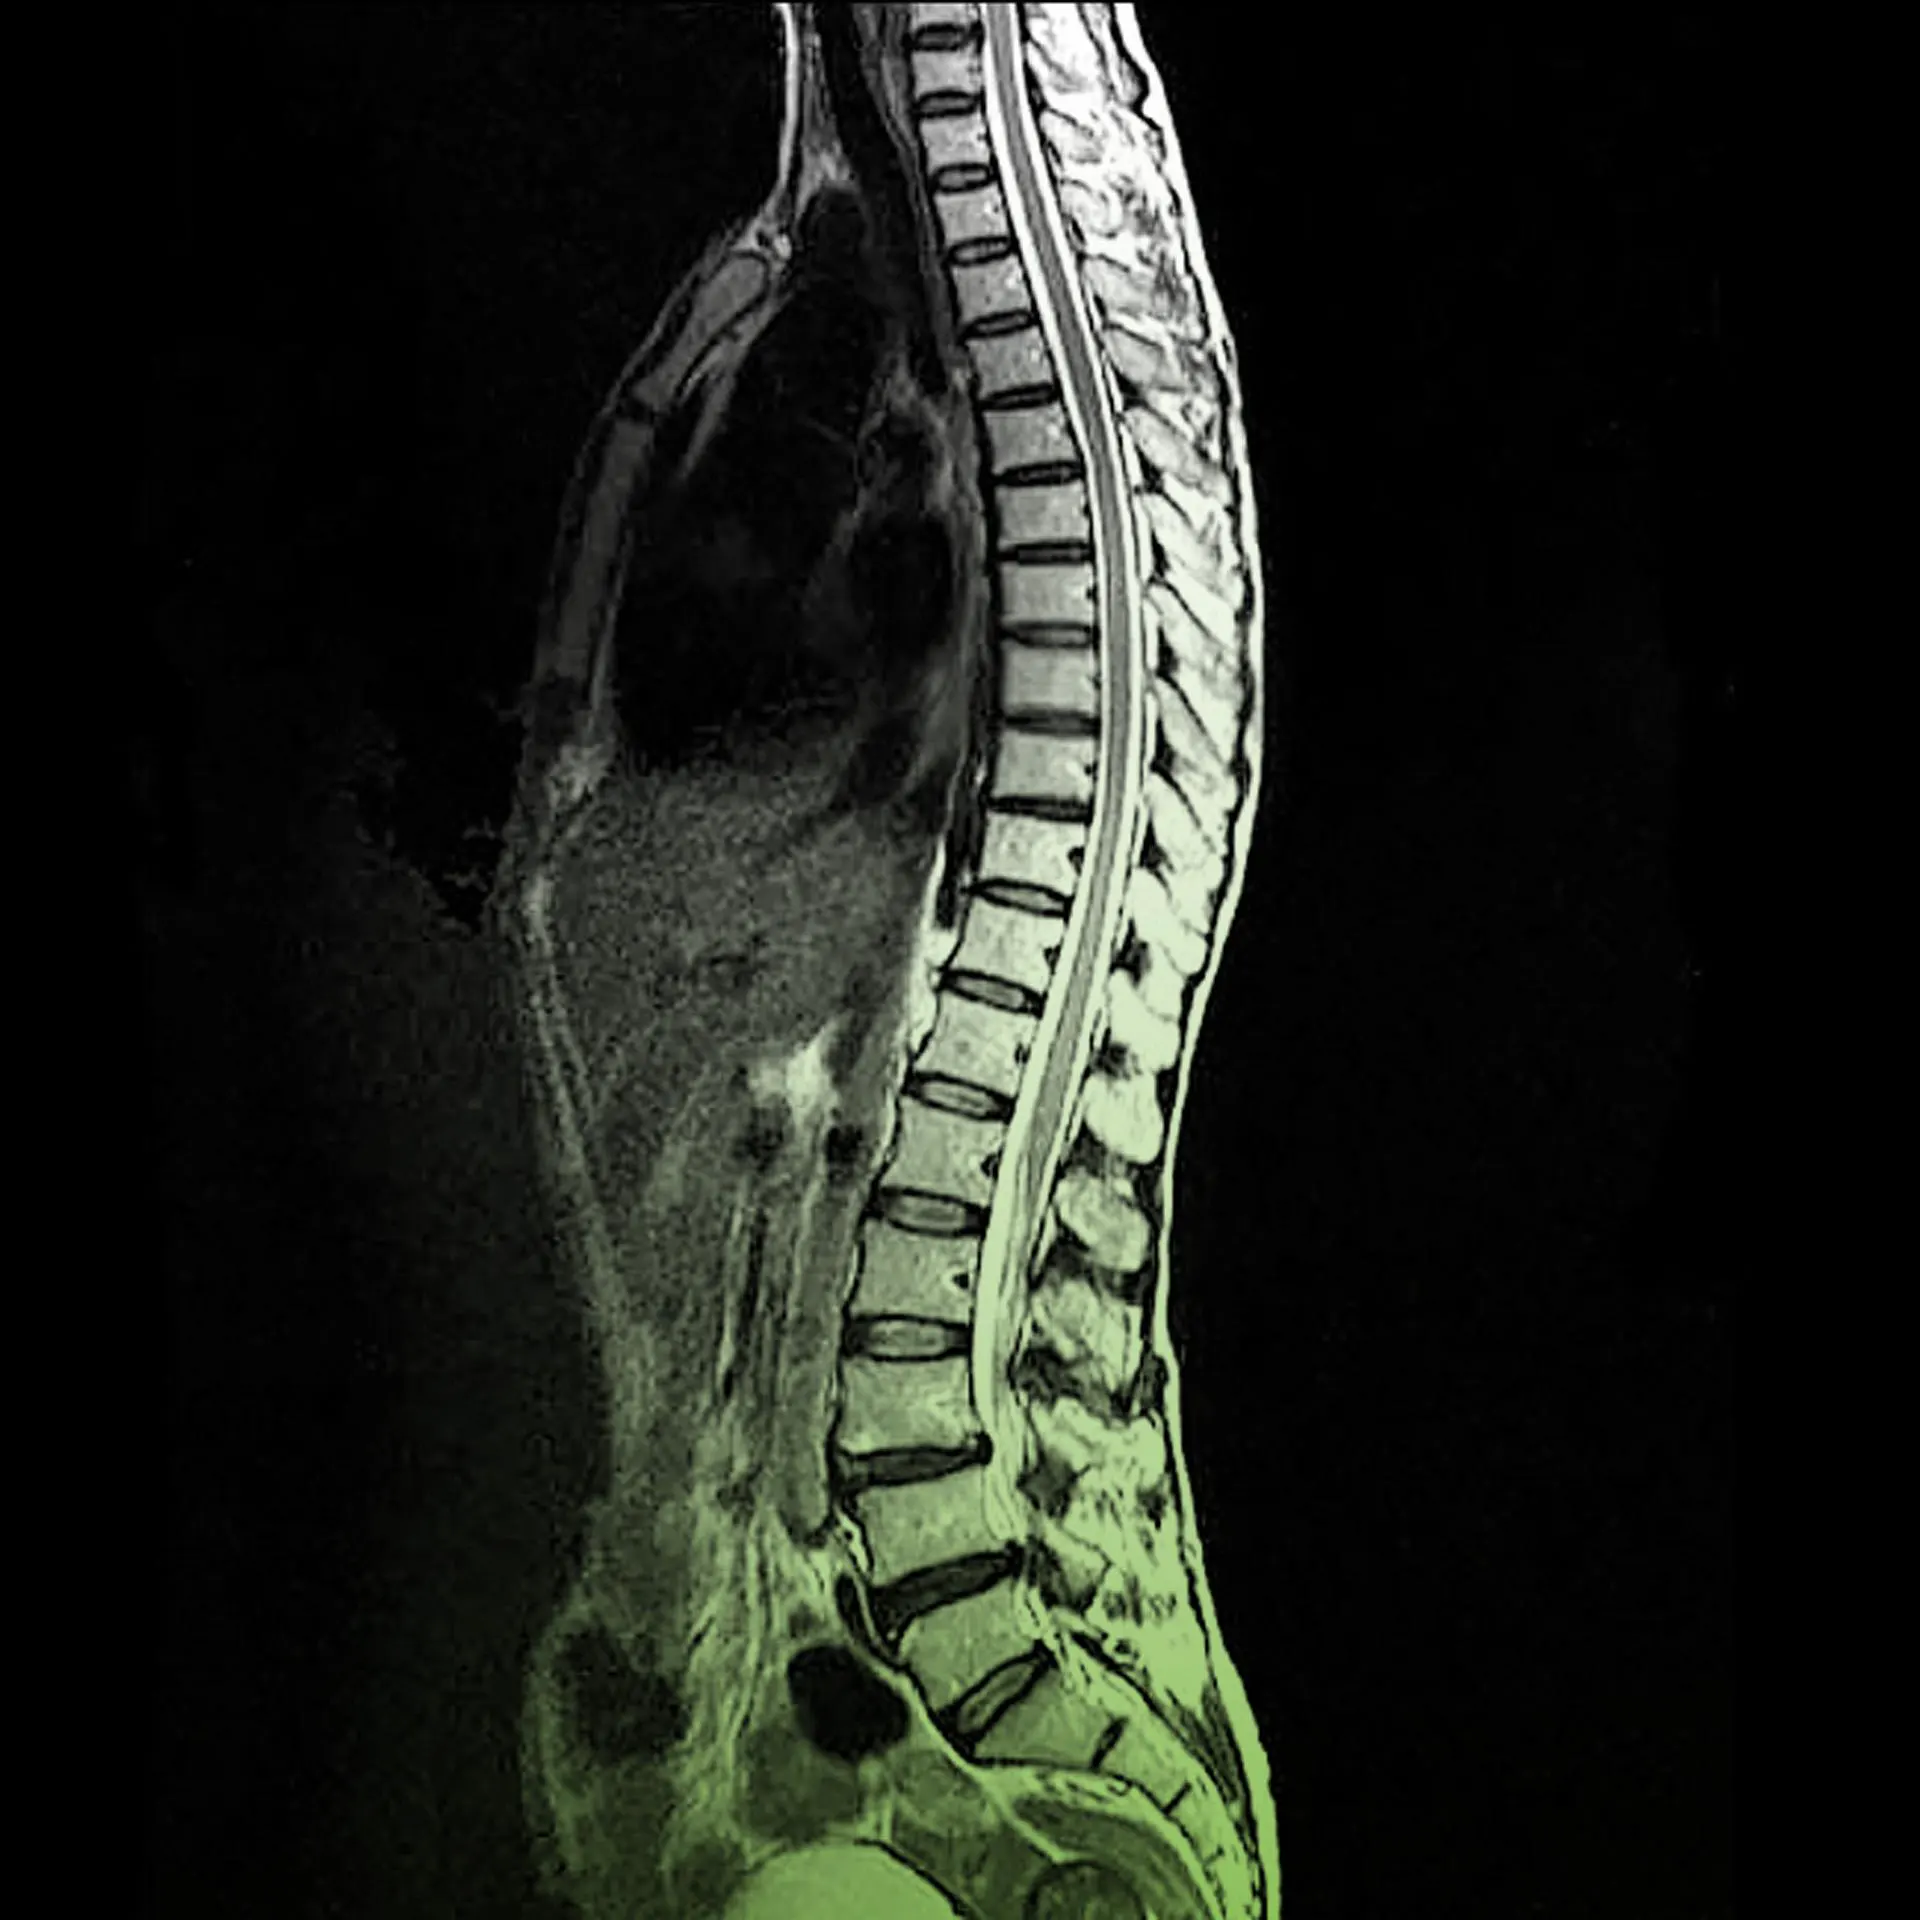

Завдяки сучасним технологіям, таким як МРТ грудного відділу хребта, діагностика стає простішою. Лікар може більше дізнатися про те, що відбувається і як діяти далі.